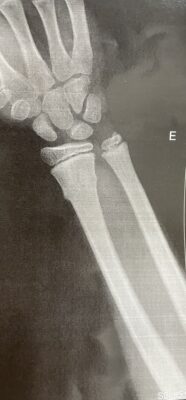

Fratura em tórus do rádio distal

• Fratura em tórus do rádio distal

Criança de 6 anos com fratura em tórus do rádio distal, sem desvio. Qual tipo de imobilização vocês mais utilizam nesses casos? Tala, gesso luva (antebraquiopalmar) ou gesso axilopalmar?

Tenho usado ortese na maioria das vezes. Só precisa ver, em crianças mais velhas, se é um torus verdadeiro no perfil. As vezes a cortical volar está rompida, um pseudo torus, e acaba ocorrendo um desvio depois de 1-2 semanas.

O que precisa ficar claro é justamente a DEFINIÇÃO de tórus, que é uma fratura com a cortical de tensão íntegra e sem desvio. É aquela que se consolida mesmo se não fizermos nada.